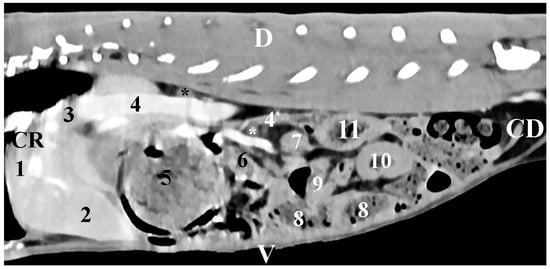

The sagittal post-contrast CT scan of regio abdominis 10 mm left to the spine showed the image of the gl. adrenalis sinistra. The gland was retroperitoneally located in the regio abdominis lateralis sinistra. The left adrenal gland was a soft tissue finding with intermediate density. The gland was observed close to the contrast-enhancing aorta abdominalis and the stomach. It was at a distance from the left kidney. The gland had an oval shape and distinct borders. The spinal muscles remained dorsal to the gland (Figure 4).

Figure 4. Sagittal CT post-contrast anatomical study of the rabbit abdomen at the level of the plane at 10 mm to the left of the spine. CR—cranial; CD—caudal; D—dorsal; V—ventral. (white star) mesenterial fold; (1) lobus hepatis sinister lateralis; (2) lobus hepatis sinister medialis; (3) fundus ventriculi; (4) corpus ventriculi; (5) left kidney; (6) pars ascendens duodeni; (7) caecum; (8) colon ascendens; (9) jejunum.